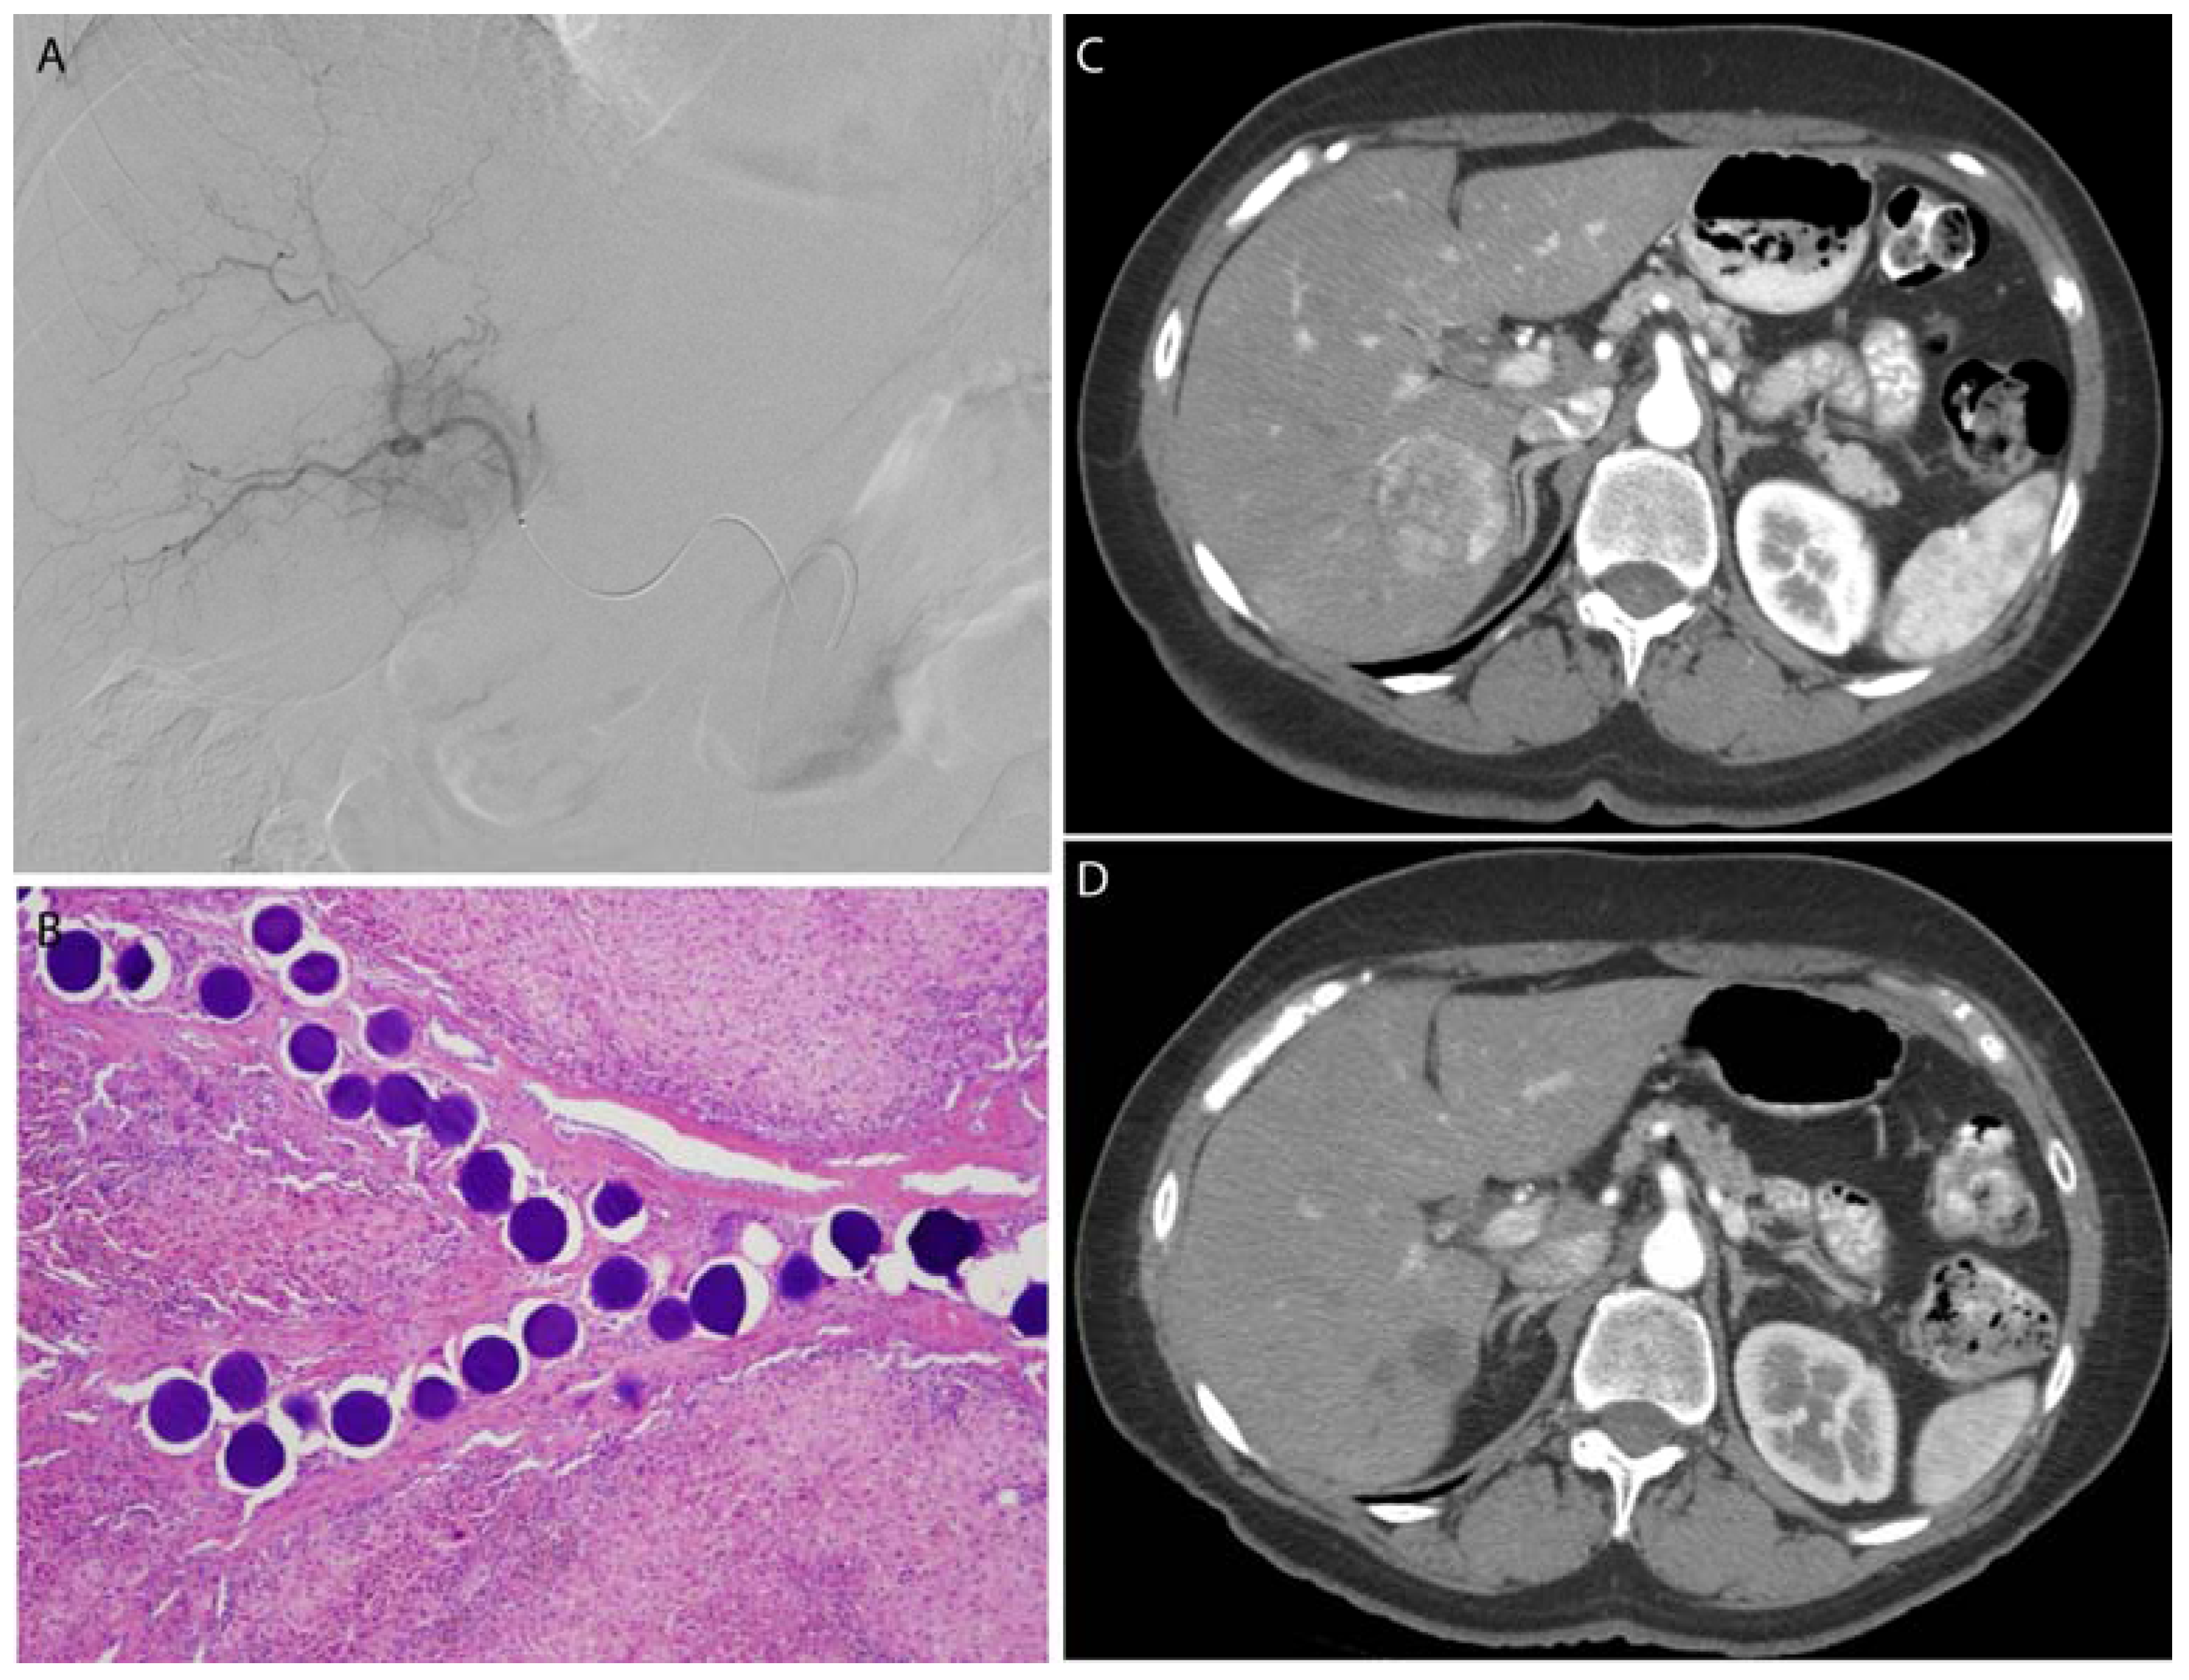

3.3. Microspheres

3.4. Drug Eluting Particles